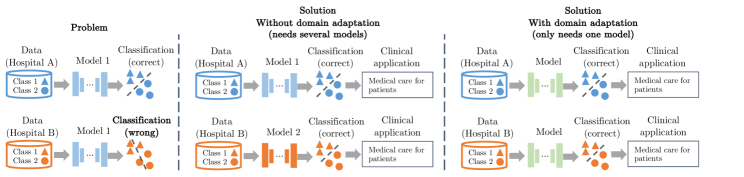

Therefore, we need domain adaptation methods to reliably transfer models from one clinical site to another and understand their error margins. Fig. 16 shows the utilization of deep learning models in clinical scenarios with and without domain adaptation.

Generalizing models across datasets with different feature distributions, i.e., domain adaptation, enables a wider and more effective utilization of deep learning models for clinical applications. This helps clinicians from different clinical sites in a wide range of geographic areas to use the same task-specific model for the analysis of their own data (e.g., obtained by different image acquisition devices), and subsequently provide diagnostic decisions and treatment suggestions to their patients. In the medical image analysis community, many previous studies (e.g., [28, 27, 15, 11, 16]) have focused on domain adaptation in different image modalities (e.g., MRI and CT) and organs (e.g., brain and heart) for various clinical applications (e.g., brain lesion and cardiac segmentation). MICCAI (the leading international conference for medical image analysis) has a dedicated session and workshops (e.g., DART) about the topic “domain adaptation”. This demonstrates that domain adaptation addresses a common problem in medical imaging and is important for various clinical applications, and thus is relevant to clinical usage and patient care.

Specifically in our work, the proposed method is applied to a real-world clinical application, the classification of standardized fetal ultrasound views during prenatal screening. Standardization of anatomical view planes is key to empower the front-line-of-care during screening, making measurements comparable across patients and to accurately predict outcomes. We focus on domain adaptation between fetal ultrasound datasets with different feature distributions, which are caused by imaging artifacts and different acquisition devices. Our study enables learning-based classifiers to be effectively utilized on a wider range of fetal ultrasound images. This helps early detection of pathological development independent from the used imaging setup. The detection of abnormalities can inform downstream treatment decisions and delivery options [25]. Fig. 17 illustrates and compares the potential impact of our method and other domain adaptation methods on machine learning for patient care in the context of fetal screening.